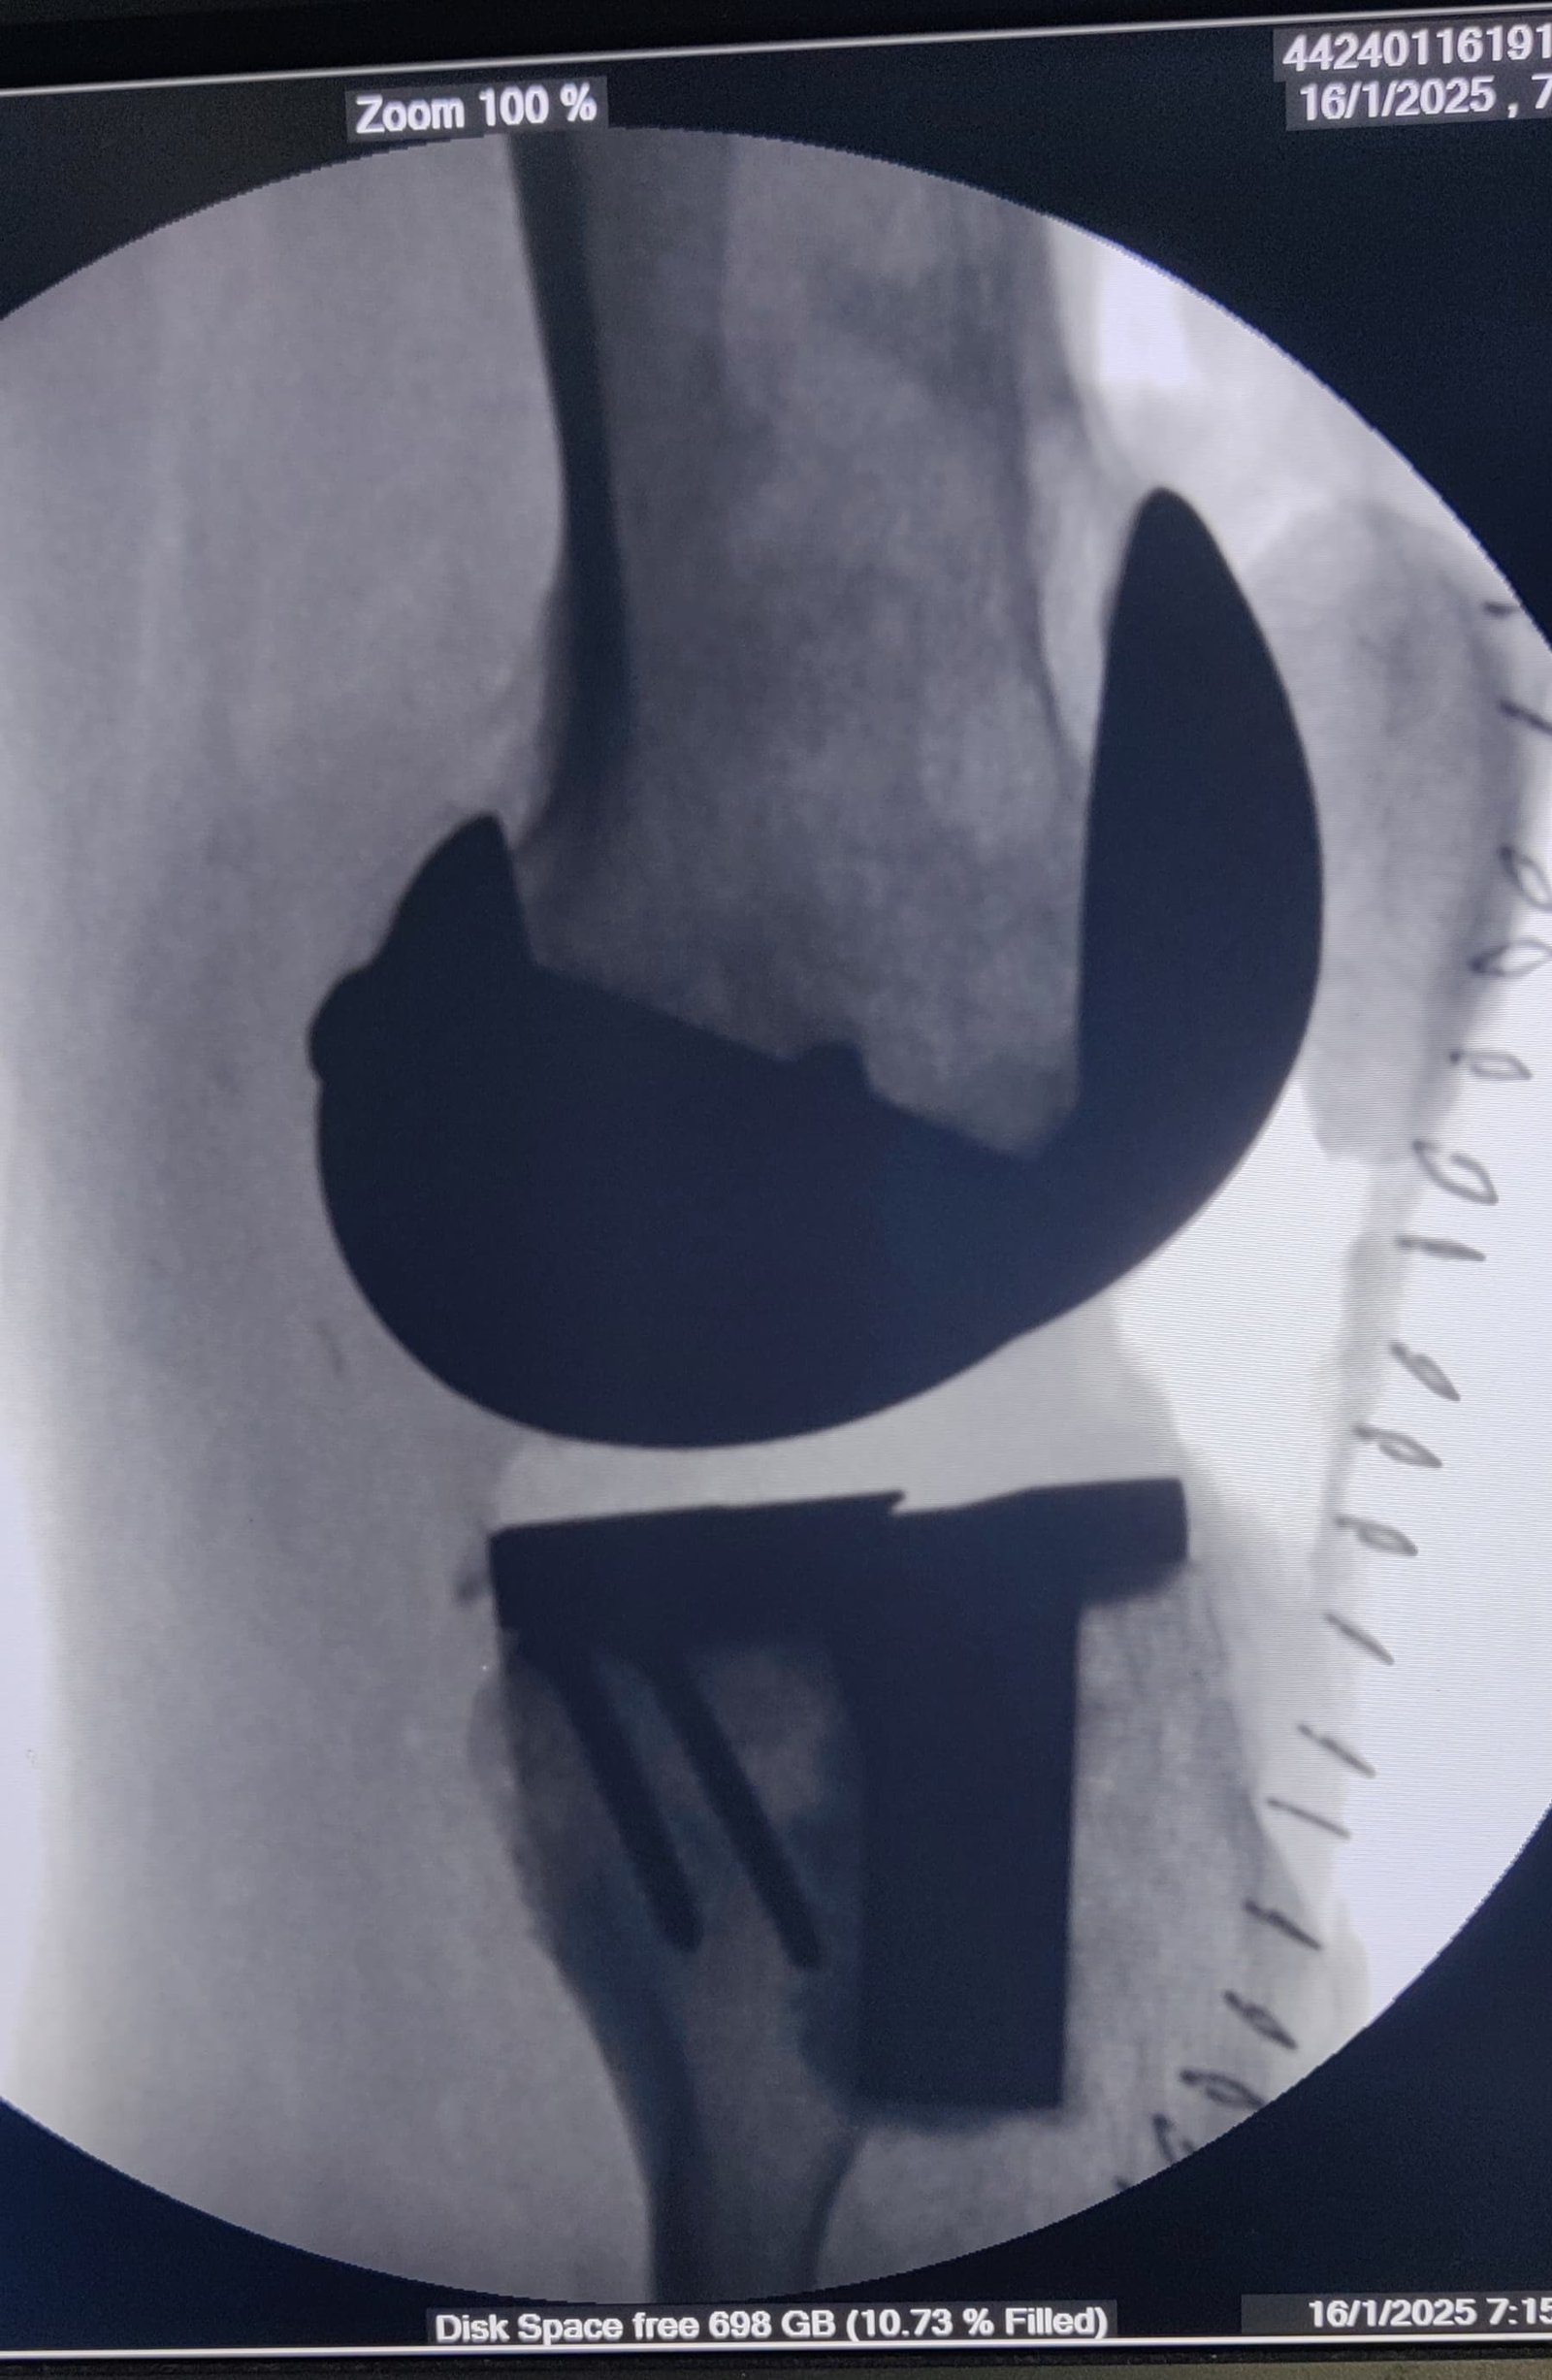

68 years lady was not walking for 5 years 8 months